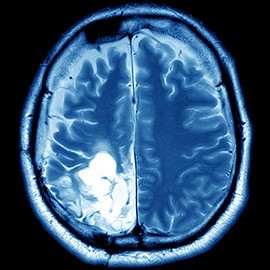

Brain Tumors

Stereotactic radiosurgery is effective for both benign and malignant brain tumors. This is the least invasive procedure for treating brain tumors. Painless and bloodless, stereotactic radiosurgery is performed as an outpatient treatment while a patient is awake.